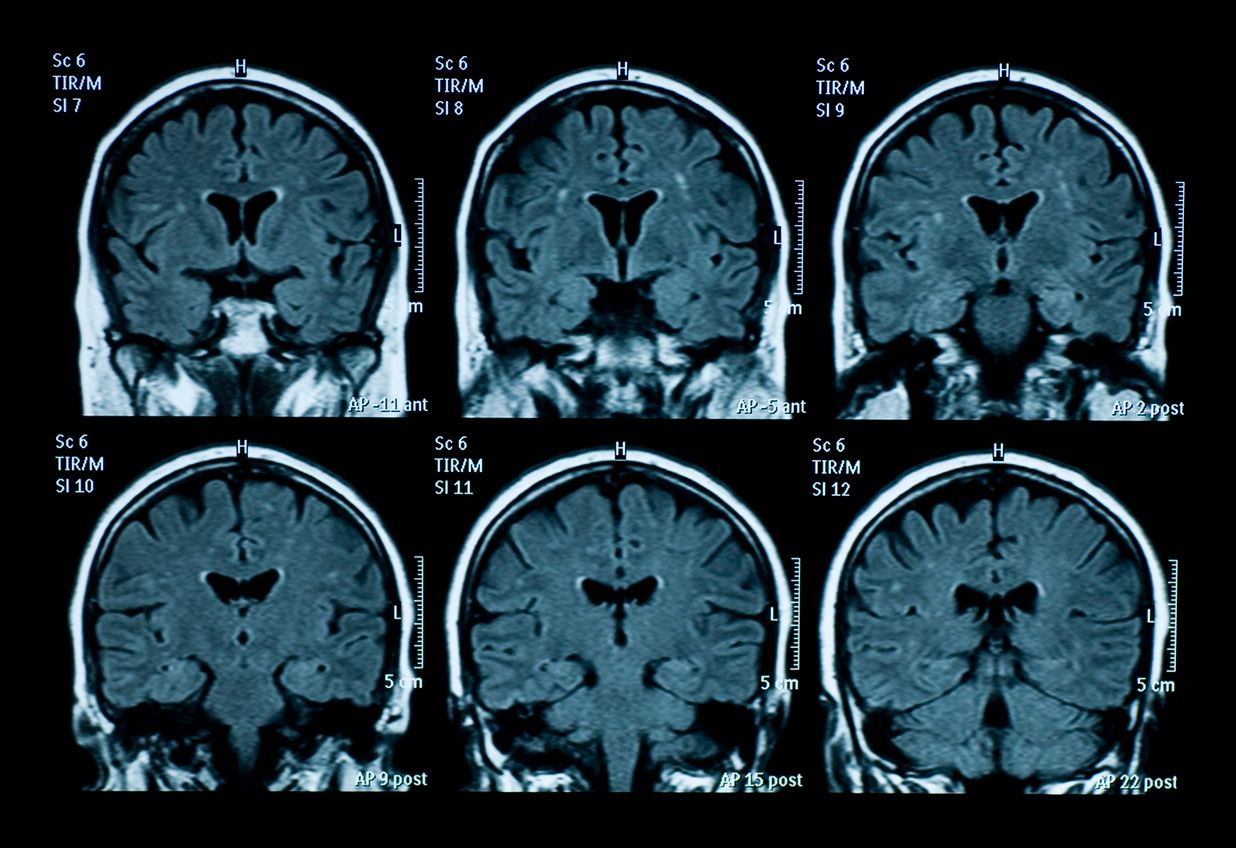

Ein 13-jähriger belgischer Junge ist der erste auf der Welt, der von einem tödlichen Gehirntumor geheilt wurde. Im Alter von sechs Jahren wurde bei Lucas Jemeljanova ein diffuses intrinsisches Ponsgliom (DIPG) diagnostiziert – ein sehr seltener und äußerst aggressiver Hirntumor, an dem 98 Prozent der Betroffenen innerhalb von fünf Jahren sterben. Im Rahmen einer klinischen Studie wurde er nach dem Zufallsprinzip mit Everolimus, einer Art Chemotherapeutikum, behandelt. Everolimus wird zur Behandlung von Nieren-, Bauchspeicheldrüsen-, Brust- und Hirntumoren eingesetzt. Bei der Behandlung von DIPG hatte es sich bislang aber nicht bewährt.

Nach Angaben des US Dana-Farber Cancer Institute wird bei etwa 300 Kindern pro Jahr ein diffuses intrinsisches Ponsgliom (DIPG) diagnostiziert. Nach der Diagnose beträgt die durchschnittliche Überlebenszeit neun Monate. DIPG tritt typischerweise bei Kindern im Alter zwischen fünf und neun Jahren auf. Diese Art von Tumor befindet sich an der Basis des Gehirns und am oberen Ende der Wirbelsäule, aber es ist nicht bekannt, was sie verursacht. Der Tumor drückt auf den Pons genannten Bereich des Gehirns, der für eine Reihe wichtiger Körperfunktionen wie Atmung, Schlaf und Blutdruck verantwortlich ist. Mit der Zeit beeinträchtigt der Tumor Herzschlag, Atmung, Schlucken, Sehkraft und Gleichgewicht. Einige der ersten Symptome des Tumors sind Probleme mit den Augenbewegungen, Gesichtsschwäche, Schwierigkeiten beim Gehen, seltsame Gliedmaßenbewegungen und Gleichgewichtsprobleme.